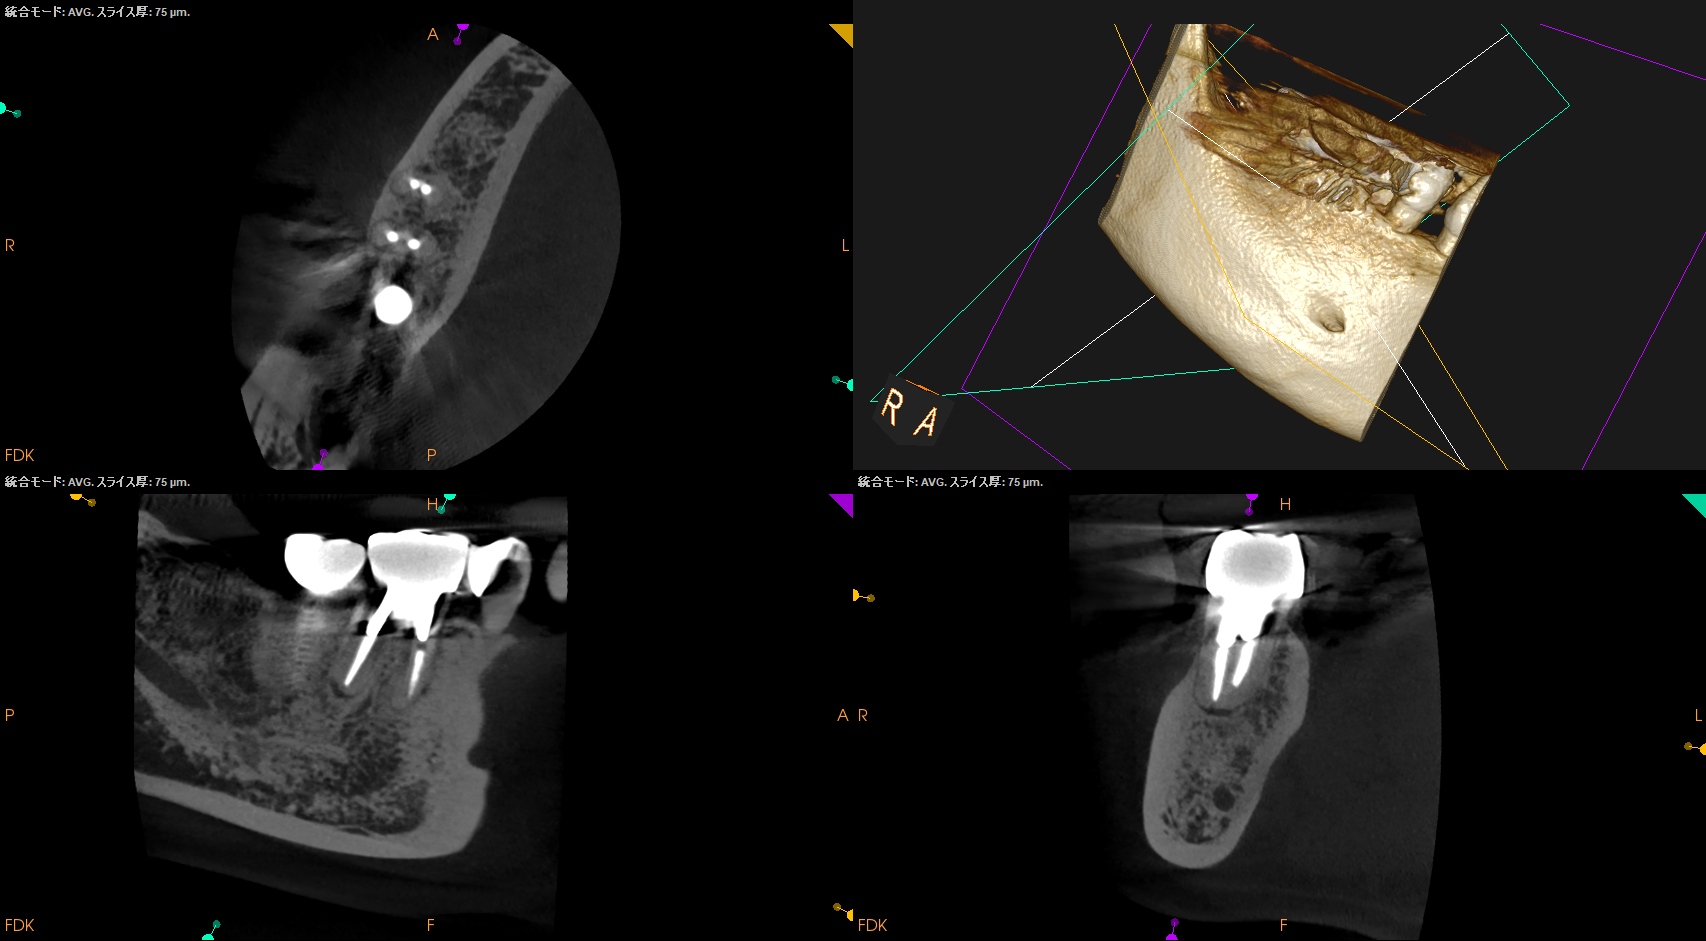

MのApexの位置を予想し、Osteotomyしていく。

その際の深さは

2mmである。

MのApexは出てくるだろうか?

見事、顔を出したのでApex-3mmで切断し、メチレンブルーで染めた。

染まった部位を逆根管形成して逆根管充填した。

下準備のおかげで非常にやりやすい外科治療であった。

最後に残存しているM根の切断部の顎を除去した。

次がDだ。

クラウンのマージン部よりも13mm下方にDのApexがある。

そこに行き着くには歯槽骨を3mm削合する必要がある。